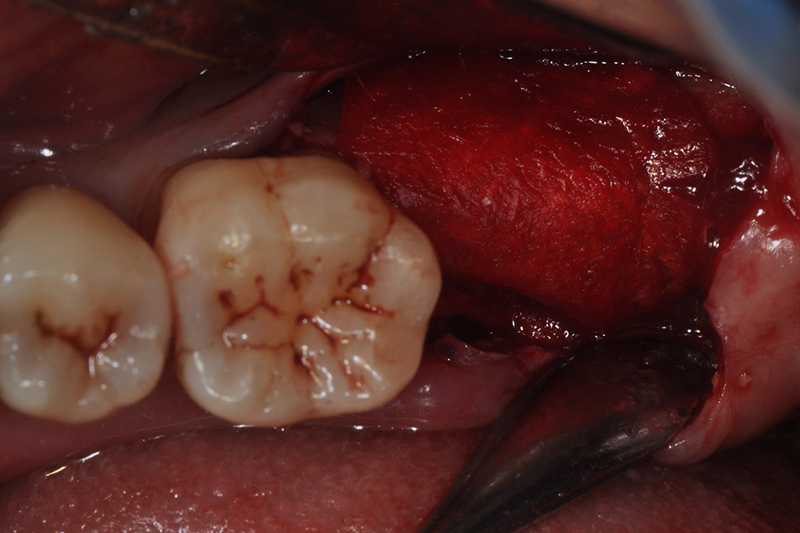

案例三

術前